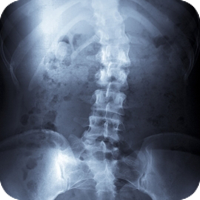

Like other health-care providers, we follow a standard routine to gain information about the patient. We consult, review the case history, conduct a physical examination, and we may request laboratory analyses and/or x-rays. Unlike other health-care providers, however, chiropractic physicians also conduct a careful analysis of the patient's structure and pay particular attention to the spine. We also ask you about your life- Do you eat well? Exercise at all? How do you deal with stress? Do you have children? What do you do for work? And so on.

Chiropractors have a term for misalignments: subluxations. A vertebral subluxation is a misalignment of the bones that protect the spinal cord. It's a leak in the roof. Or a kink in the wiring of your nervous system. The severity of the subluxation can vary, and there are a number of potential contributing factors that can be physical, emotional, mental, or chemical. The subluxation can be caused by any number of incidents, from birth trauma to an auto accident to simple repetition or over-use.